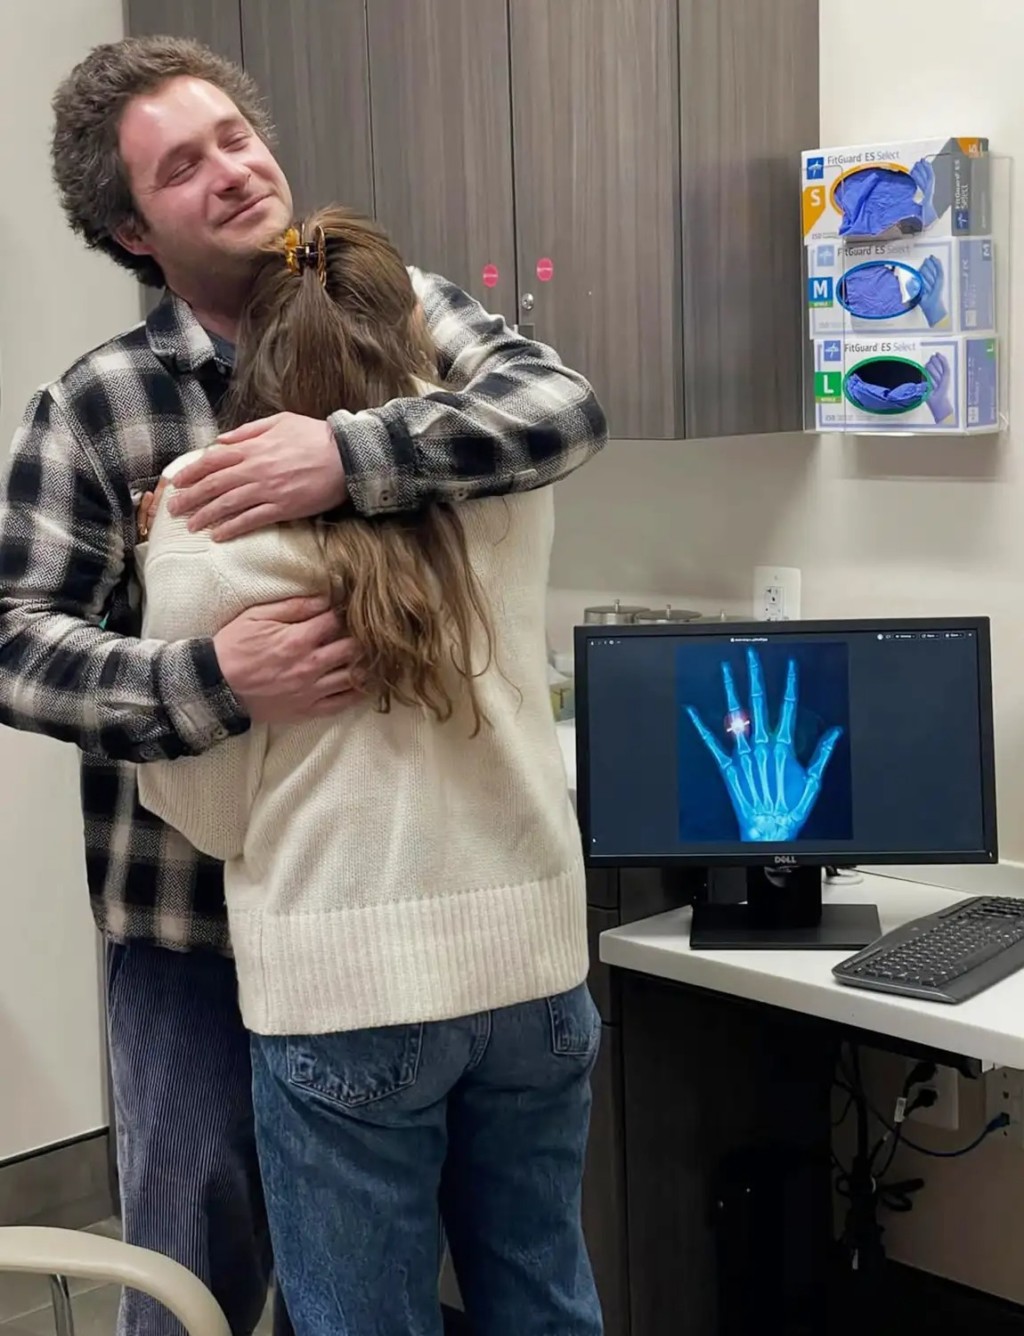

根據《時人》報導,當天賈斯汀幫忙預約看診並陪著女友進診間,安娜伊絲覺得男友很體貼,完全沒有起疑。3位醫護人員進診間時,安娜伊絲還想說只是個小傷,怎麼需要那麼多人來。當醫師在螢幕上秀出一張左手X光片,安娜伊絲才驚喜發現,X光上的無名指竟然多一枚戒指。這對情侶交往2年,賈斯汀幾個月前就想求婚了,早就準備好一枚3.47克拉的鑽戒,但遲遲等不到開口的好時機。

直到這天女友摔傷手,賈斯汀靈機一動決定在CityMD診所求婚,迅速向醫護人員說明求婚計畫,提前取得醫療團隊的幫助。安娜伊絲看到X光後,賈斯汀拿出戒指單膝下跪求婚成功。安娜伊絲感動落淚:「感覺好不真實!賈斯汀的求婚太神奇了,我這輩子從沒那麼驚喜過!」

翻攝自CityMD

CityMD首席營運長納維恩·鄧克利 (Navienne Dunkley) 表示團隊很榮幸能參與這場求婚,稱讚賈斯汀的絕妙點子,「祝福這對新人一生健康幸福!」其實這對準夫婦跟醫院緣分不淺,兩人從小住附近,但直到2年前透過朋友介紹才認識。